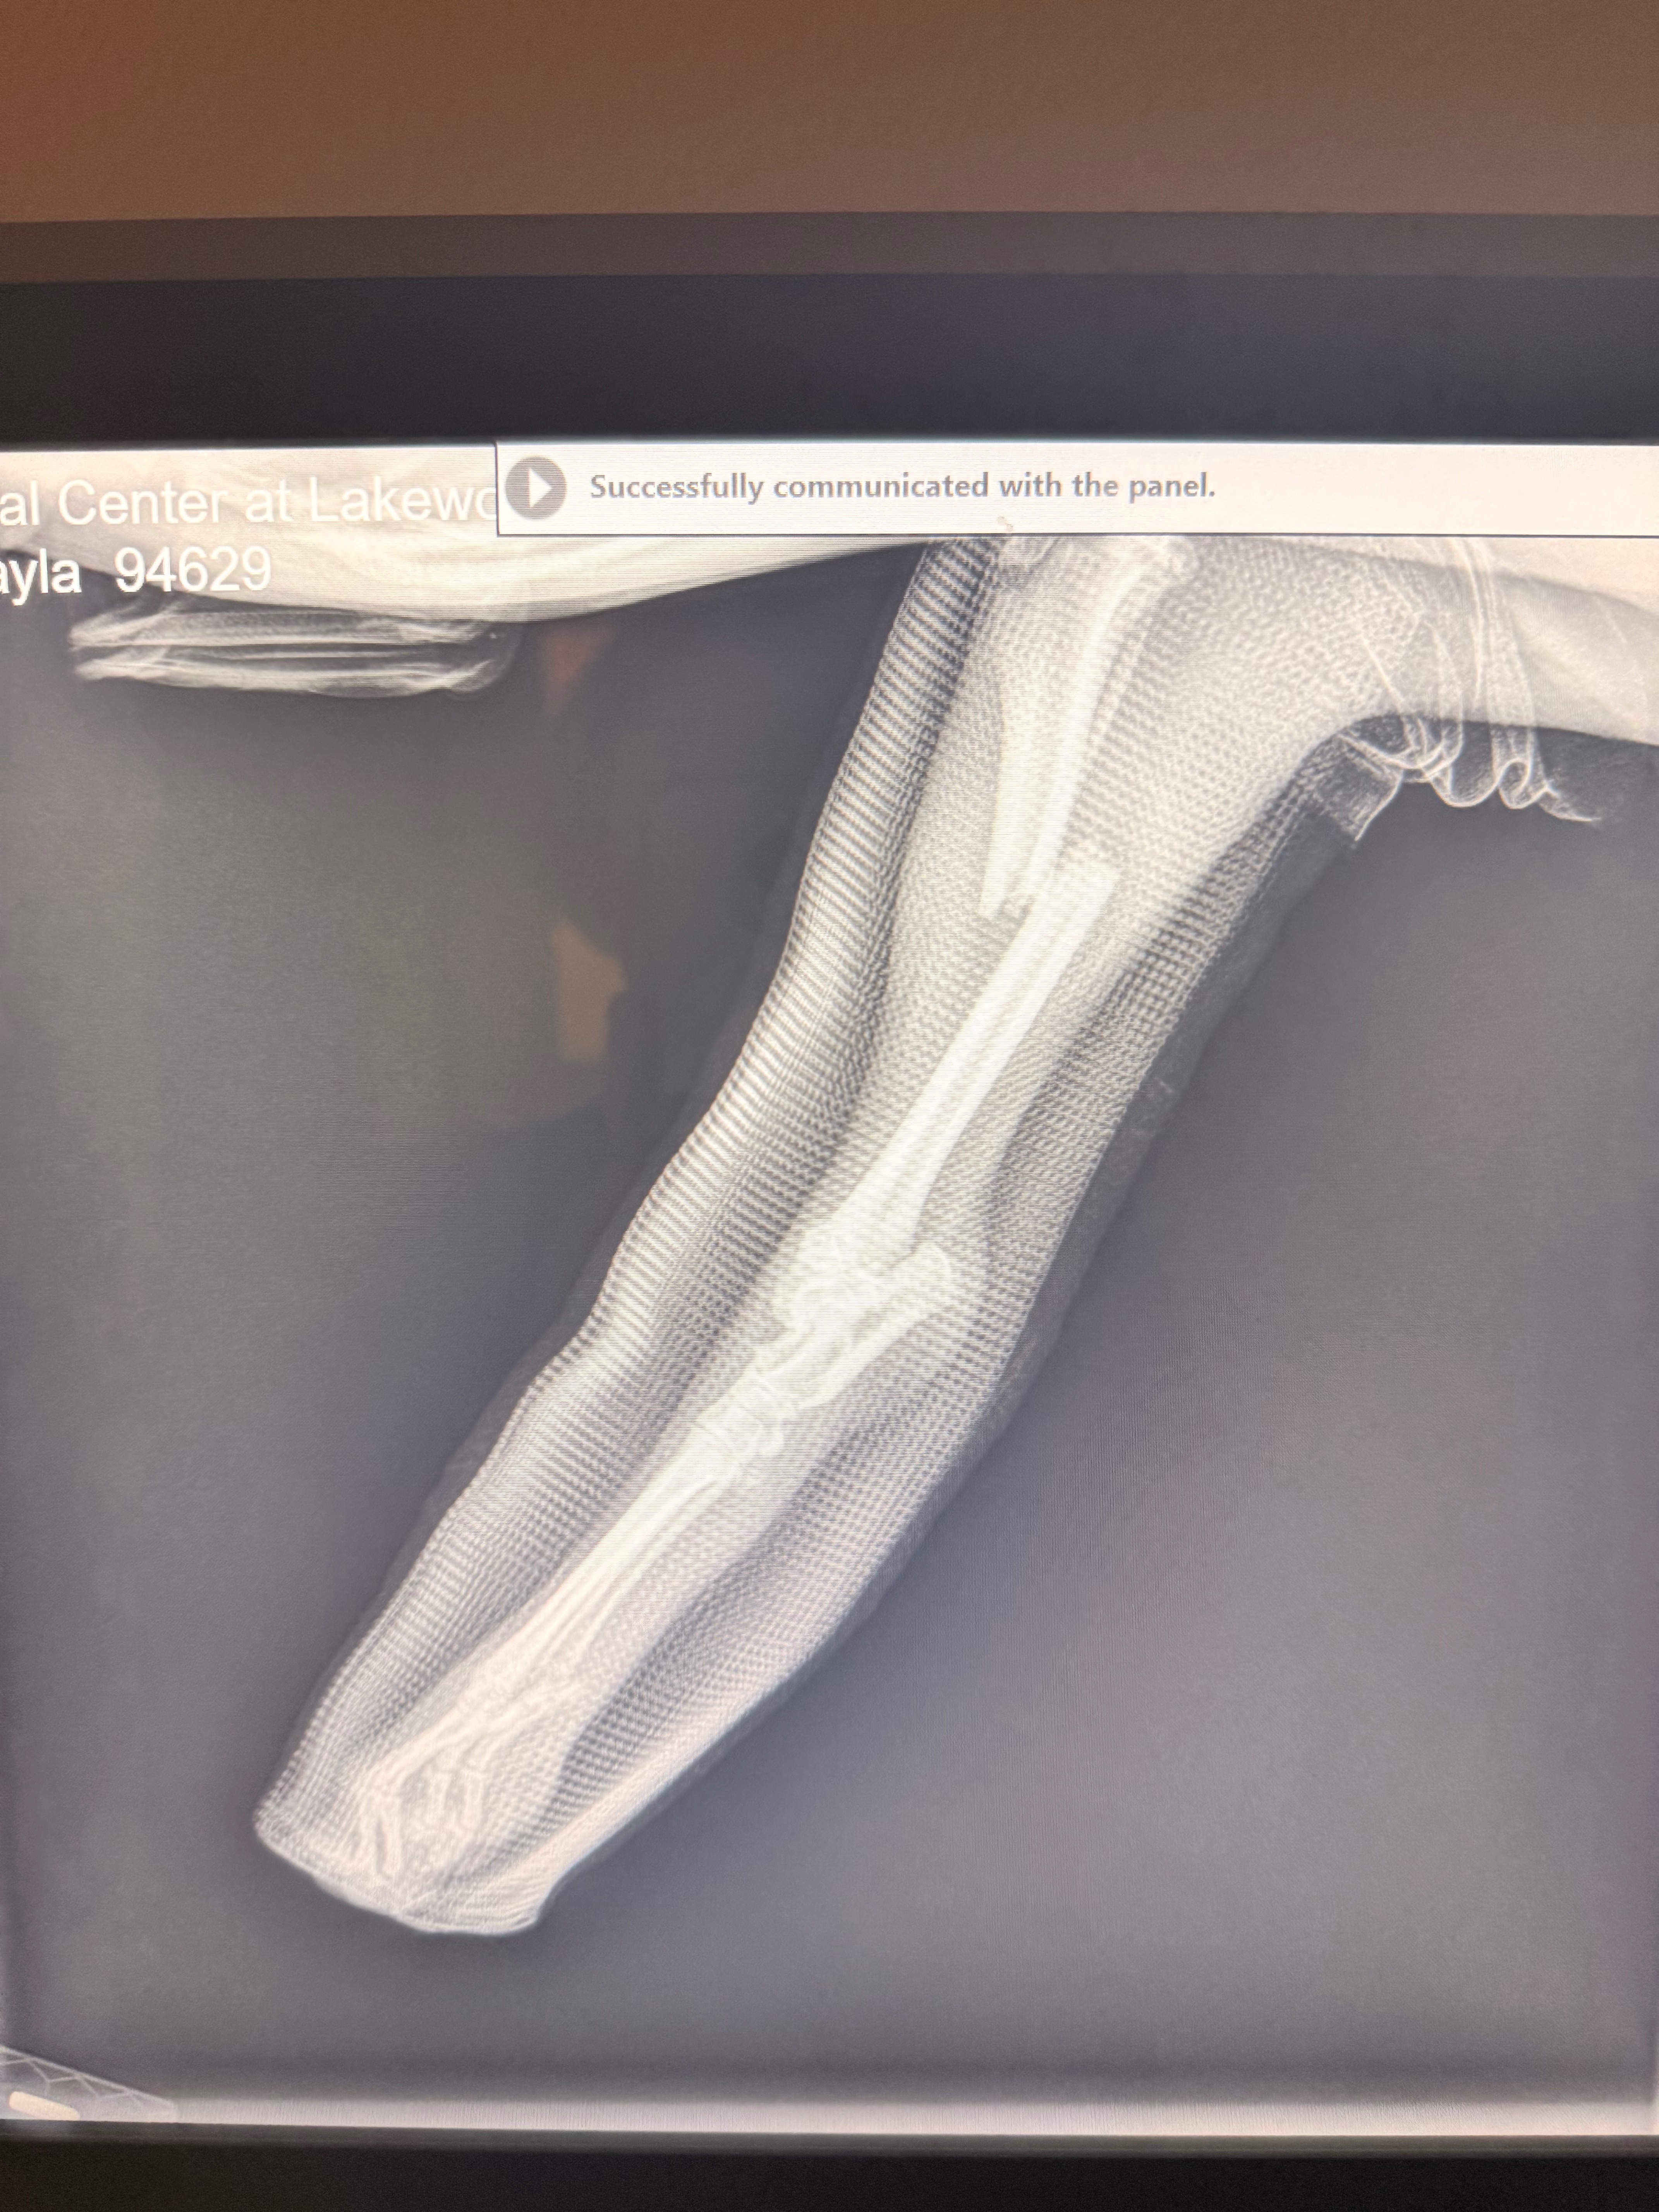

Rescued from Miami-Dade Animal Services, this sweet baby girl came to us with what was thought to be a healing broken leg. Unfortunately, their X-ray machine was down, so everyone hoped the cast she arrived in was doing its job.

But once we brought Shayla to VMC at Lakewood Ranch, the truth came out…

Her leg is completely broken.

And not just one break — she’s facing a major, painful injury.